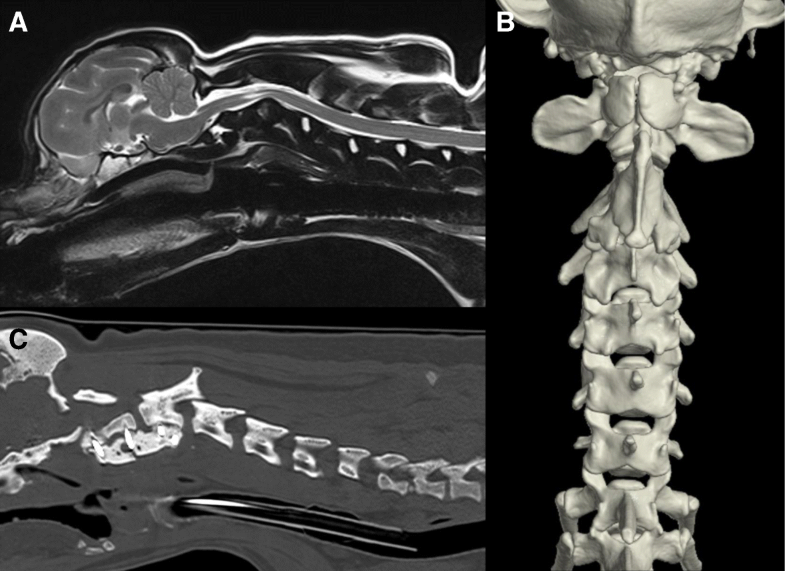

From irishvetjournal.biomedcentral.com

Cervical vertebral malformations in 9 dogs radiological findings, treatment options and Dog Neck Vertebrae Clinical presentations include cervical, thoracolumbar, and lumbosacral localizations. cervical spinal problems in dogs: It can range in severity, from pain to paralysis. Canine intervertebral disk disease (ivdd) is the most commonly seen spinal disorder. this article discusses the many manifestations of this disorder and current therapeutic recommendations. A pain in the neck. my dog was suddenly unable. Dog Neck Vertebrae.